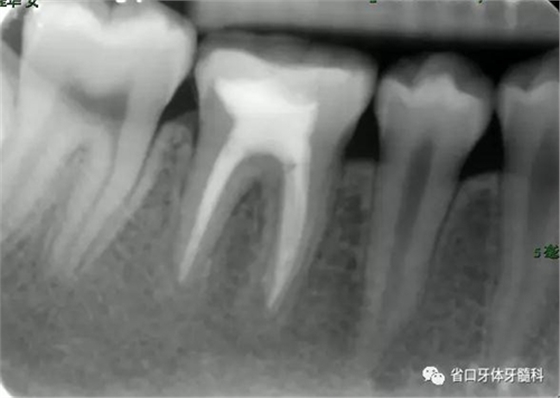

檢查:46牙合面牙色充填物,叩+,松I度,探及頰舌側根分叉處牙周袋深及根尖區(qū),頰側牙齦略腫脹。

圖1 初診X片示根尖周及根分叉大范圍低密度影像

診斷:46牙髓牙周聯(lián)合病變(牙髓源性)